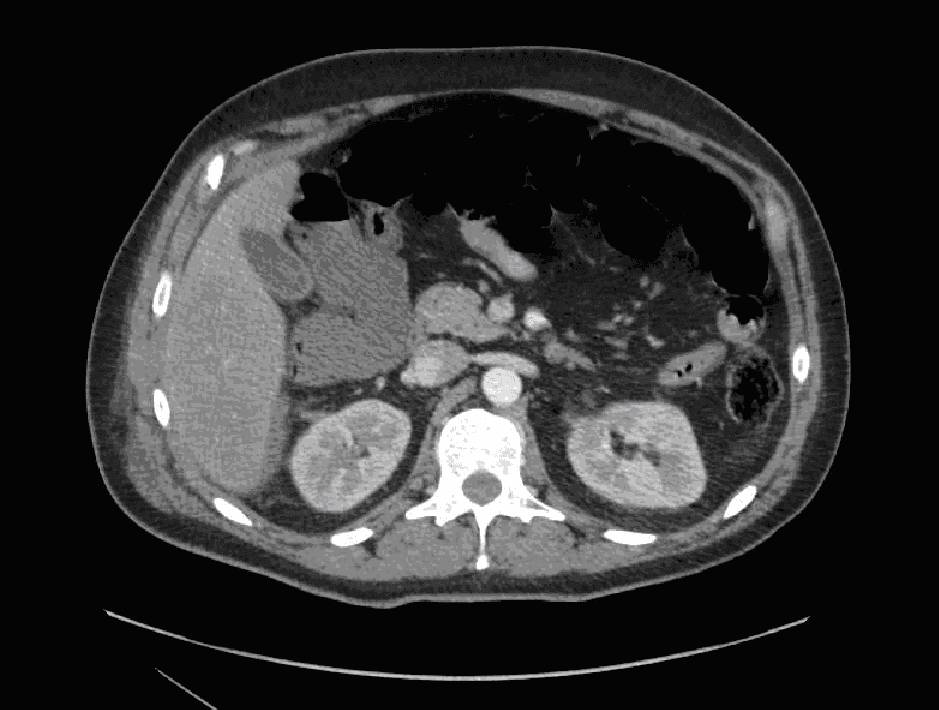

Upon arrival at the Level 1 Trauma Center, the patient remained tachycardic and demonstrated localized right lower quadrant peritonitis. A repeat E-FAST exam was positive for intraperitoneal free fluid in Morison’s pouch (see Figure 1). After further resuscitation, the patient was hemodynamically stable enough to undergo CT imaging of the abdomen/pelvis. The CT demonstrated a large right-sided retroperitoneal complex fluid collection measuring 82 x 132 x 172 mm that extended from the posterior pararenal space to the peritoneal fat anteriorly. Mottled locules of gas were evident within the collection, suspicious for traumatic colonic perforation. There was also fluid in Morison’s pouch (see Figure 2), consistent with what was seen on the E-FAST exam. As such, the patient was emergently taken to the Operating Room (OR) for exploratory laparotomy.